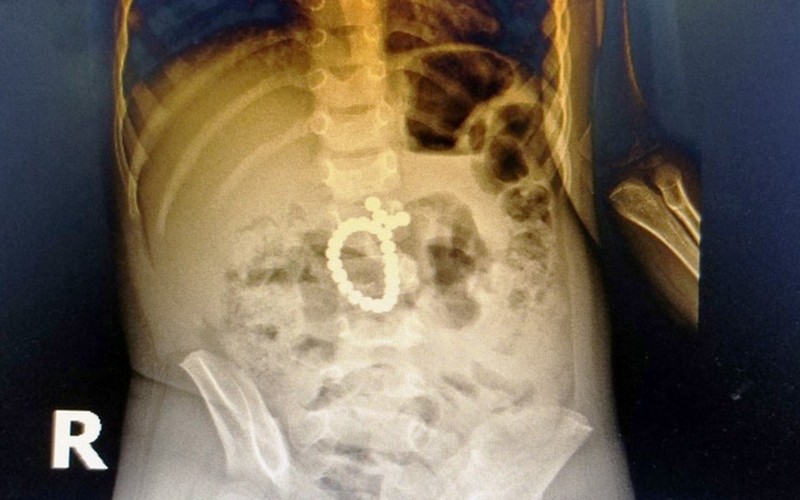

Nghệ An: Cứu bệnh nhân nhi nuốt 25 viên bi nam châm, thủng ruột và tá tràng

Ngày 6/1, Bệnh viện Sản Nhi Nghệ An cho biết, các y, bác sĩ bệnh viện vừa phẫu thuật cấp cứu thành công bệnh nhi 3 tuổi, trú tại thành phố Vinh do nuốt phải 25 viên bi nam châm đồ chơi vào ổ bụng.

Ngay sau khi tiếp nhận, qua các xét nghiệm và X-quang ổ bụng bệnh nhi, các bác sĩ đã phát hiện bệnh nhân bị tắc ruột do dị vật hình tròn, bao gồm nhiều viên nhỏ và dính thành chuỗi. Các bác sĩ khoa Ngoại và khoa Gây mê hồi sức tiến hành hội chẩn và chỉ định mổ cấp cứu.

Trong quá trình phẫu thuật, các bác sĩ đã phát hiện 25 viên bi nam châm dính chặt vào nhau gây tắc nghẽn ruột, khiến tá tràng và ruột bệnh nhi thủng nhiều vị trí. Sau gần 3 giờ, các phẫu thuật viên đã loại bỏ hoàn toàn dị vật, khâu kín vị trí ruột thủng thành công.

25 viên bi nam châm dính chặt vào nhau gây tắc nghẽn ruột, khiến tá tràng và ruột bệnh nhi thủng nhiều vị trí. (Ảnh: Yến Phương)